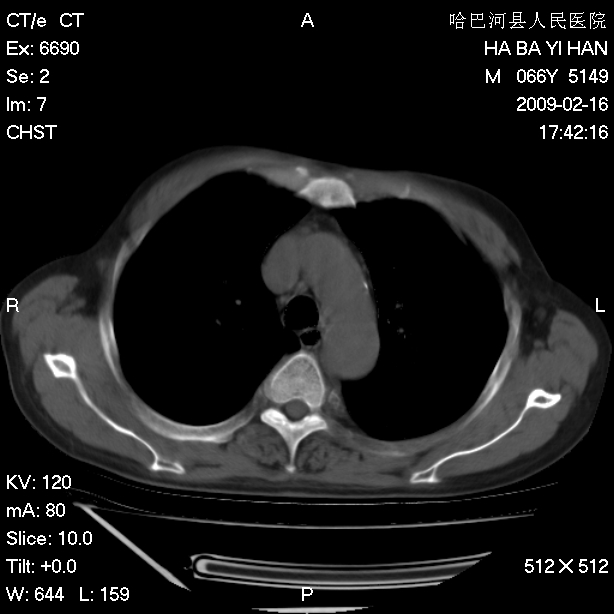

以下是引用huangxun4321在2009-2-16 20:18:00的发言:[br]部分病灶可见硬化边,部分可见骨质破坏消失,部分病灶内可见骨脊,说明病灶内既有良性病变,又有恶性病变,考虑骨巨细胞瘤恶变,未除骨纤恶变,畸形性骨炎少见,亦要考虑.

以下是引用731208在2009-2-16 20:31:00的发言:[br]考虑恶性胸膜间皮瘤并肋骨,脊柱转移。

以下是引用yijiansheng在2009-2-16 20:16:00的发言:[br]考虑恶性胸膜间皮瘤并肋骨,脊柱转移。

以下是引用形影不离在2009-2-16 19:55:00的发言:[br]考虑多发性转移瘤。